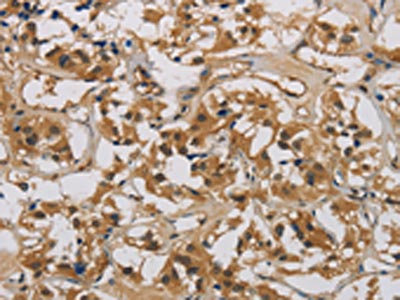

The image is immunohistochemistry of paraffin-embedded Human gastric cancer tissue using CSB-PA785649(CASP9 Antibody) at dilution 1/70. (Original magnification: ×200)

The image is immunohistochemistry of paraffin-embedded Human thyroid cancer tissue using CSB-PA785649(CASP9 Antibody) at dilution 1/70. (Original magnification: ×200)